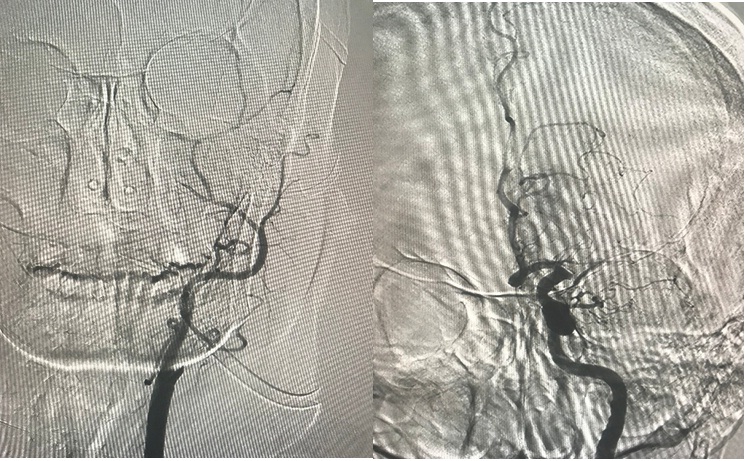

Hình: ĐM não giữa trái trước và sau lấy huyết khối